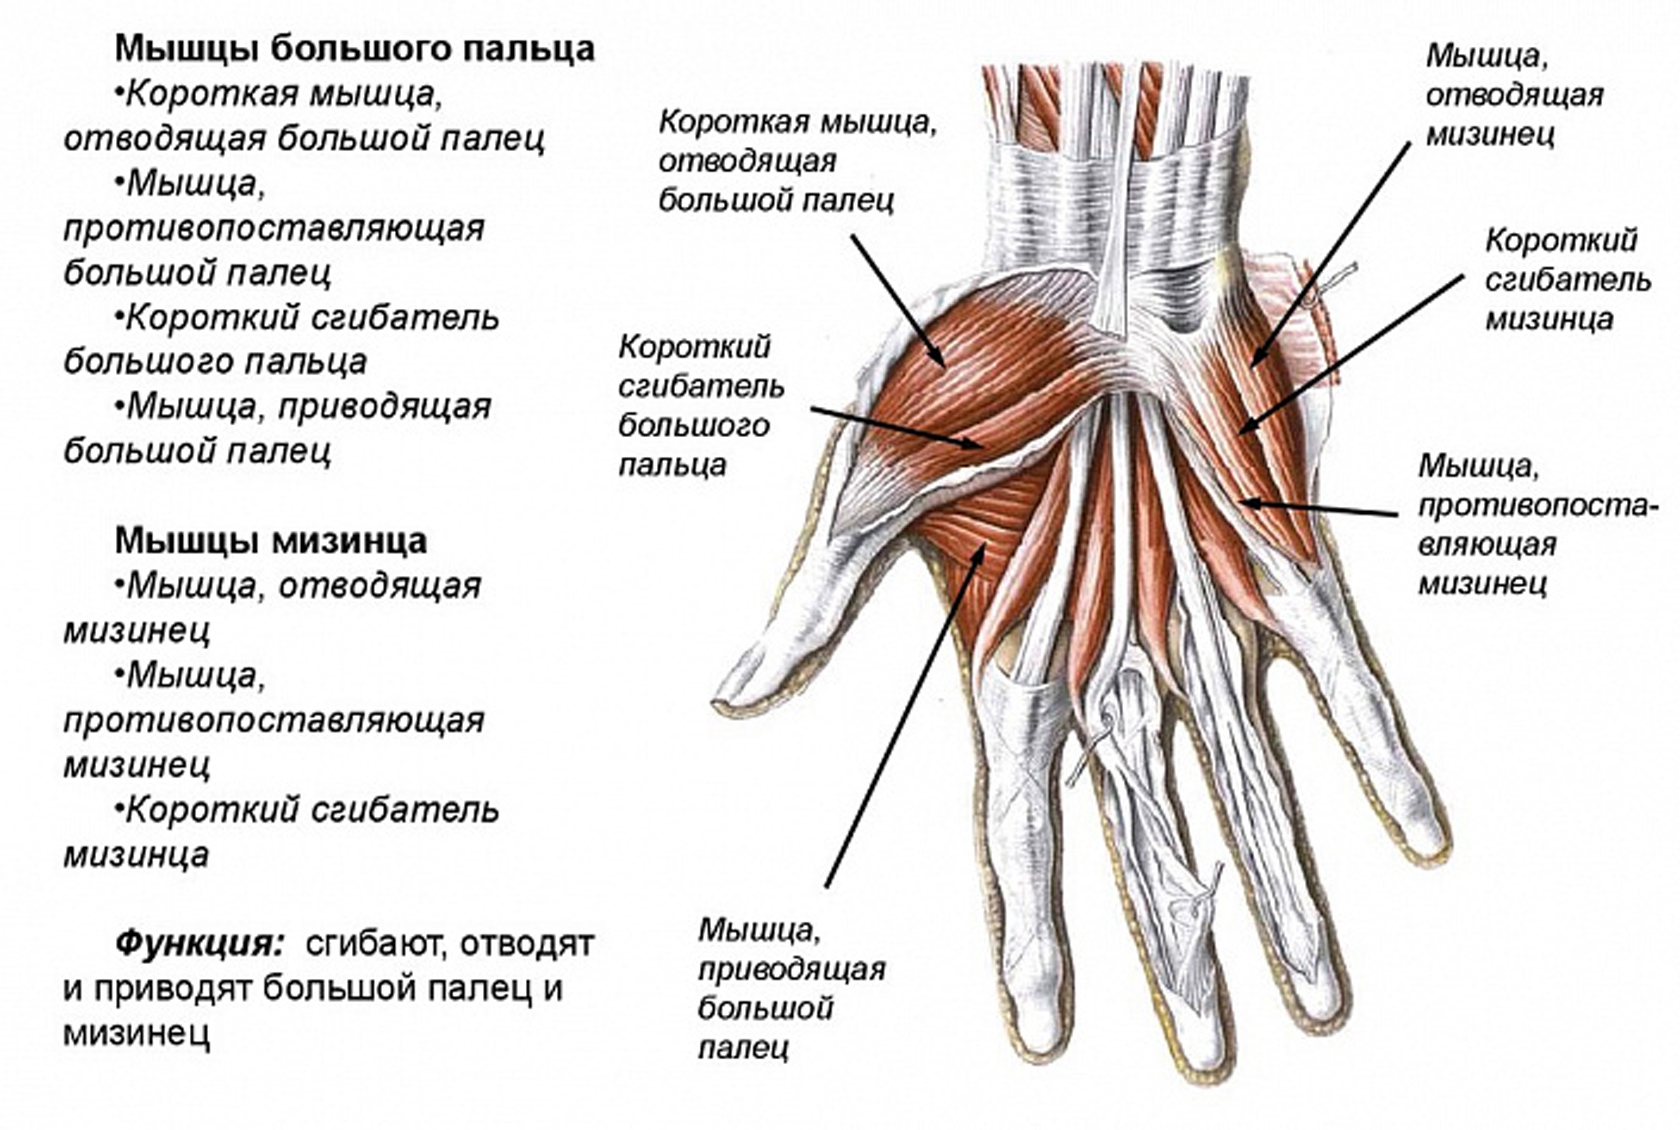

Анатомия кисти руки и строение костей